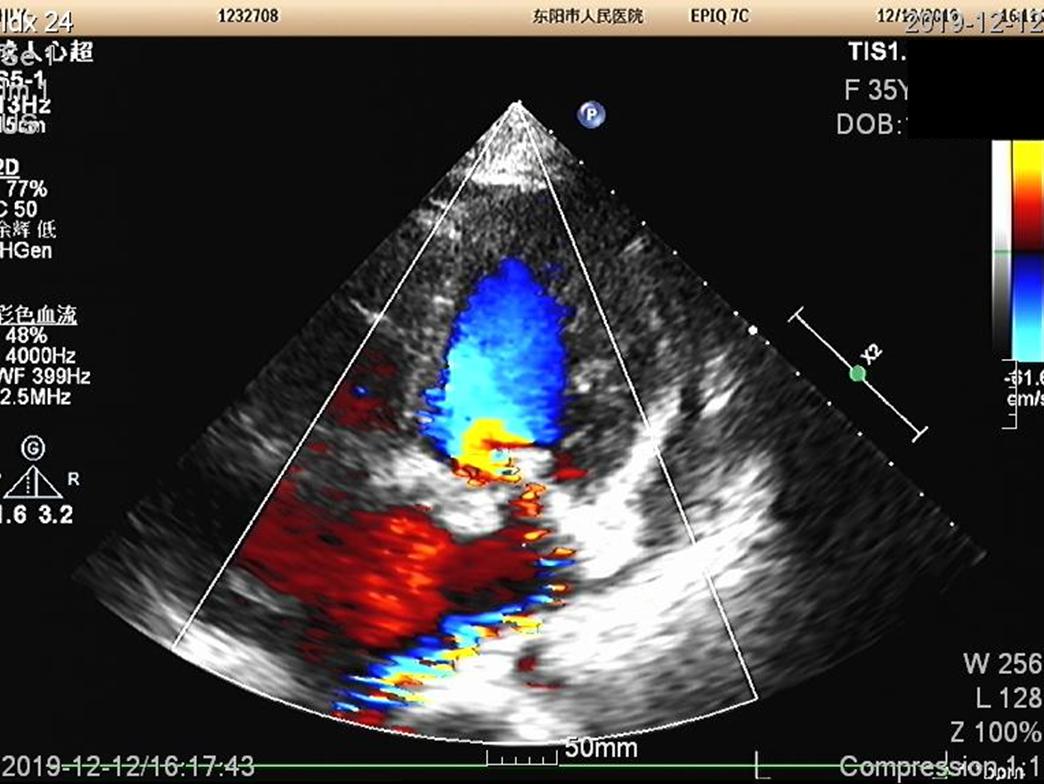

心超心尖四腔心切面,多普勒超声可见二尖瓣返流、返流束较窄。 二尖瓣存在前叶A2、A3区脱垂。

胸骨旁左室长轴切面,显示二尖瓣上有赘生物,这赘生物其他多个切面也可以观察到。

另结合患者血培养阳性,为草绿色链球菌,故诊断明确,为亚急性感染性心内膜炎。

这脾肾肠多脏器加上右髂总动脉,都为心源性栓塞,栓子为二尖瓣赘生物脱落的菌栓。